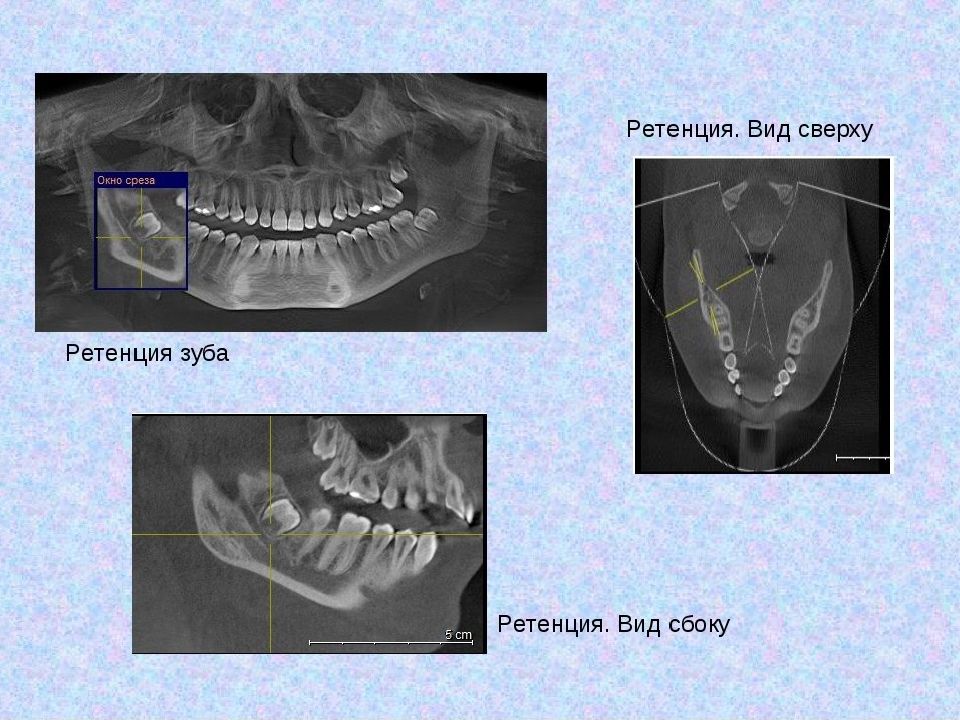

Слайд 24: Конусно-лучевая компьютерная томография — полуретенция зубов 1.8, 2.8, 3.8, 4.8, дистопия зубов 2.8, 4.8

• Конусно-лучевая компьютерная томография — полуретенция зубов 1.8, 2.8, 3.8, 4.8, дистопия зубов 2.8, 4.8